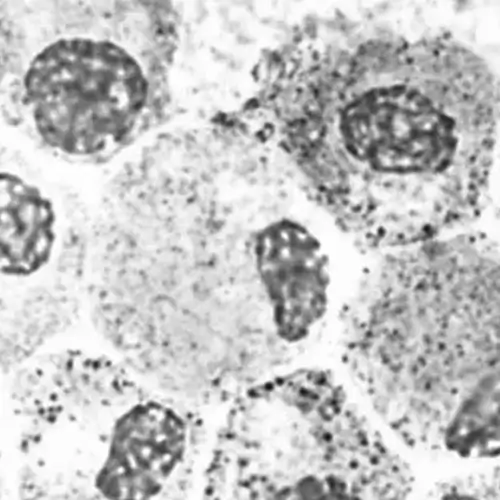

We provide cryopreserved suspension hepatocytes that are thoroughly characterized for high viability and general phase I and phase II metabolism activities in short-term suspension metabolic pathways. Each batch undergoes extensive quality control procedures, and detailed reports can be provided upon request.

These transporter qualified suspension hepatocytes are ideally suited for short-term in vitro drug clearance assays, with a recommended usage time of less than 4 hours. However, it's important to note that these suspension hepatocytes are not suitable for assays that require adherent cells.

These pre-characterized cells offer a cost-effective and straightforward test system for in vitro metabolite identification and studies related to metabolic stability. Each cell lot is accompanied by a proper Certificate of Analysis, ensuring the highest quality standards for your research needs.